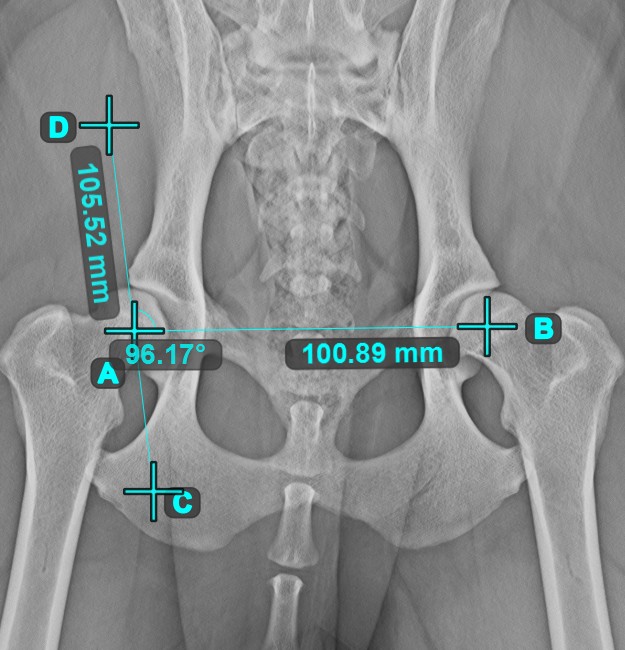

Angle of Lines

Calculate the angle between two independent or intersecting lines by using the Angle of Lines tool.

Select the tool from the left toolbar and assign it to one of the available mouse buttons. Start by selecting the first line from the ones already drawn on the scene, or place the start and end points to create the line. Follow the same steps for the second line of the measurement. The angle between the two lines will be automatically calculated.

Modify the start and end points of both lines by using the Select/Move Item tool. The angle between the two lines will be automatically recalculated.

Information

If two lines do not intersect directly, the angle of their extended projections on the scene will be calculated.

../_images/image7.jpg ../_images/image312.jpg